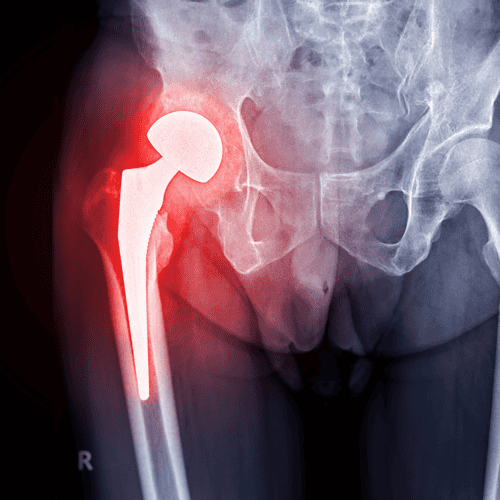

The Ultimate Guide to Hip Resurfacing Surgery in Mexico

Hip resurfacing surgery in Puerto Vallarta provides Alberta patients with an effective, affordable alternative to full hip replacement. Modern techniques and skilled specialists help restore mobility and improve long-term joint function.